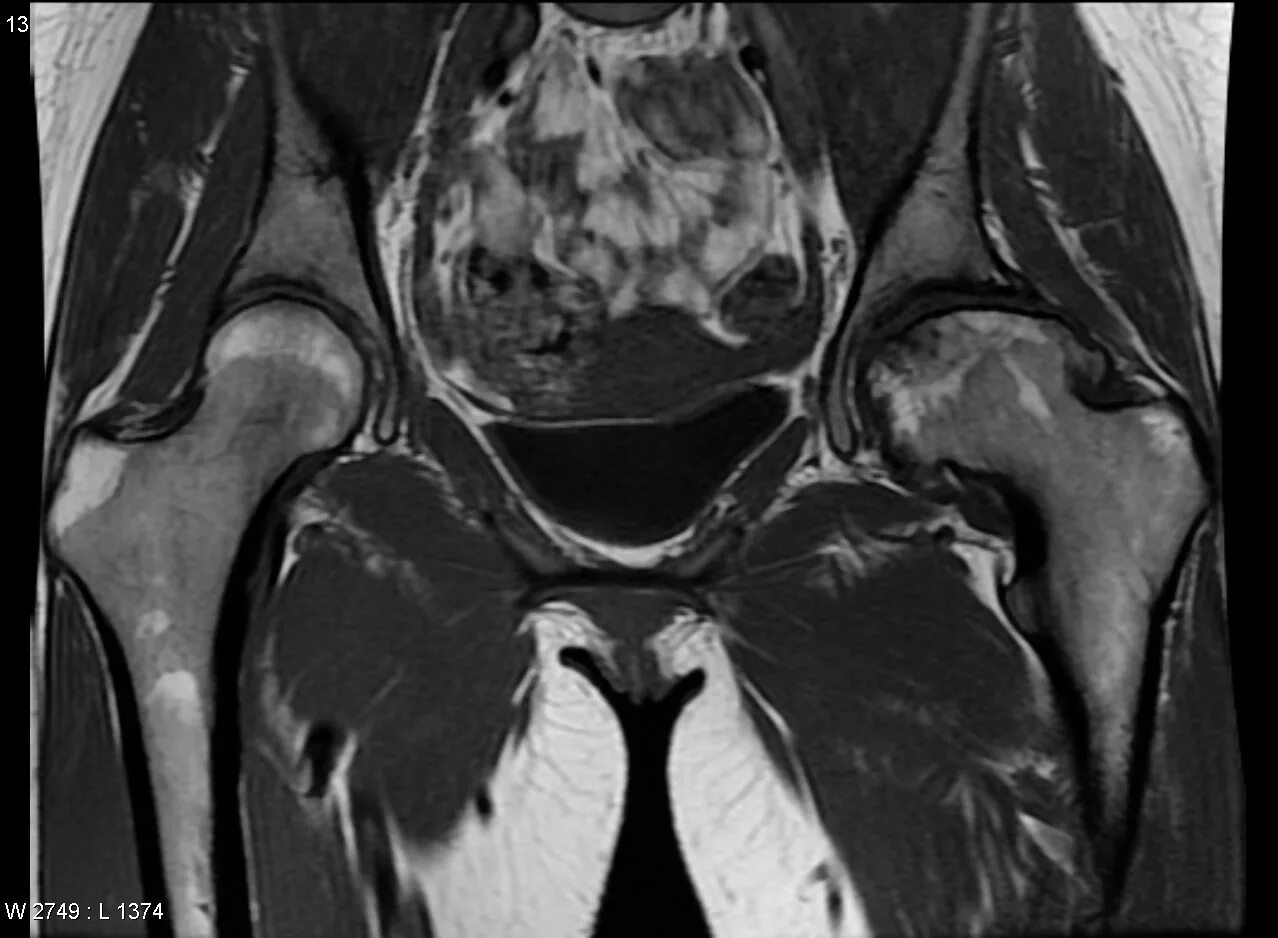

Мрт тазобедренного сустава в минске